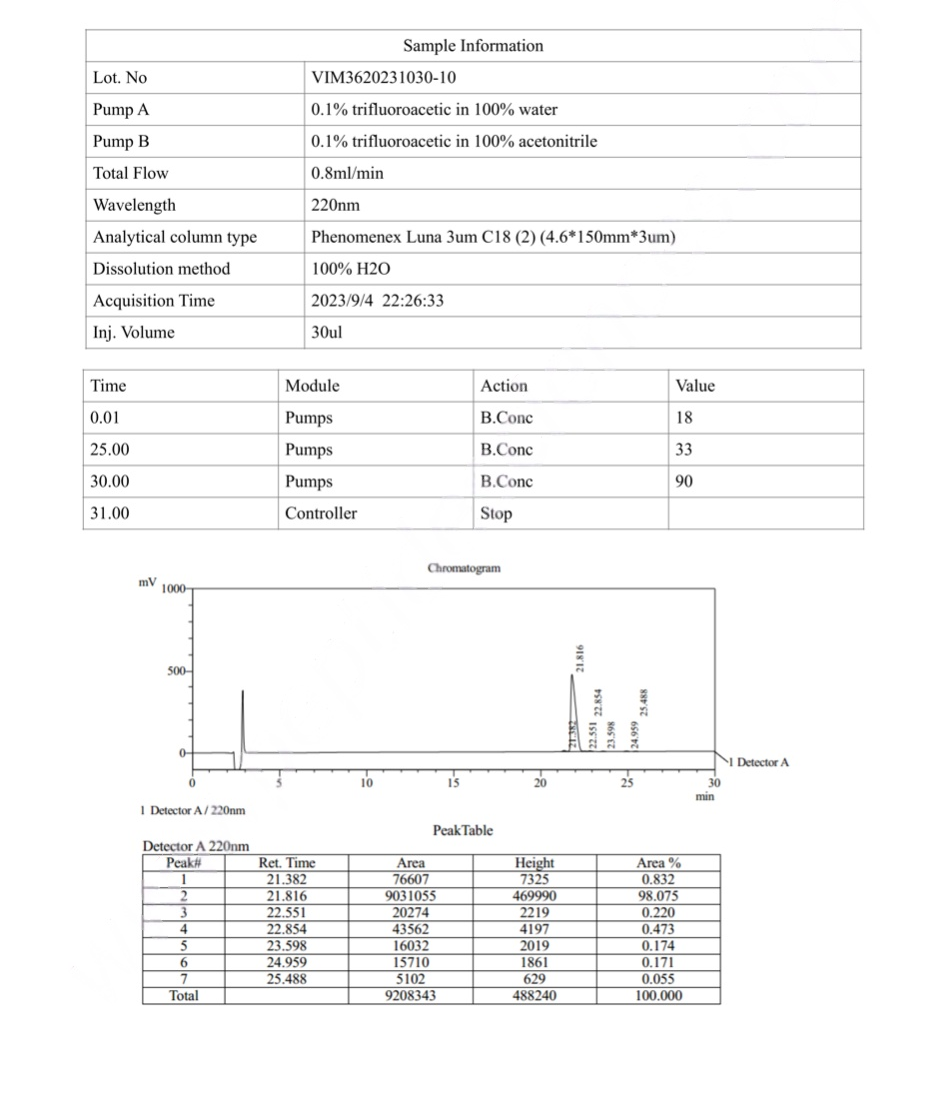

Adipotide (FTPP) COA CERTIFICATE

HPLC Adipotide (FTPP) Certificate